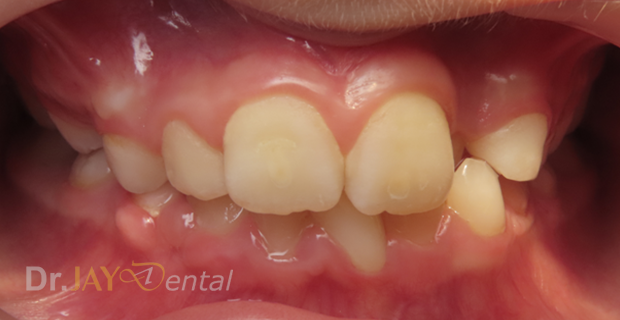

Patient had issue with spacing needed for erupting teeth , patient still going through treatment. After picture : in 6 months with Myofunctional therapy and tongue tie revision , jaws are widening and teeth are having space to erupt

Before

After